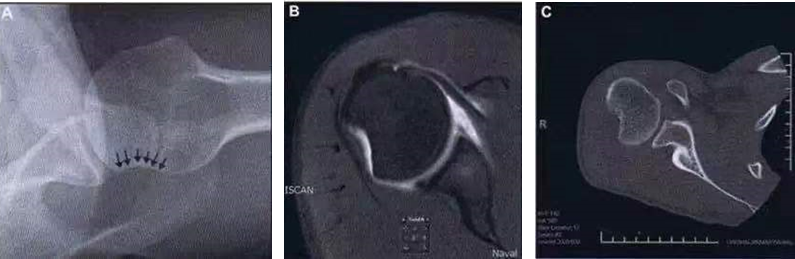

(2) Hill-Sachs、反 Hill-Sachs 损伤

肩关节脱位时,肱骨头和关节盂发生撞击,肱骨头表面凹陷性骨折。

肩关节前脱位时发生的肱骨头后外侧凹陷性骨折,是经典的 Hill-Sachs 损伤(Hill-Sachs lesion);而肩关节后脱位时发生的肱骨头前内侧凹陷性骨折,是反 Hill-Sachs 损伤(Reverse Hill-Sachs lesion/ McLaughlin lesion)。

A.Hill-Sachs 损伤的 X 片;B.Hill-Sachs 损伤的 MR 片;C.Hill-Sachs 损伤的 CT 片。